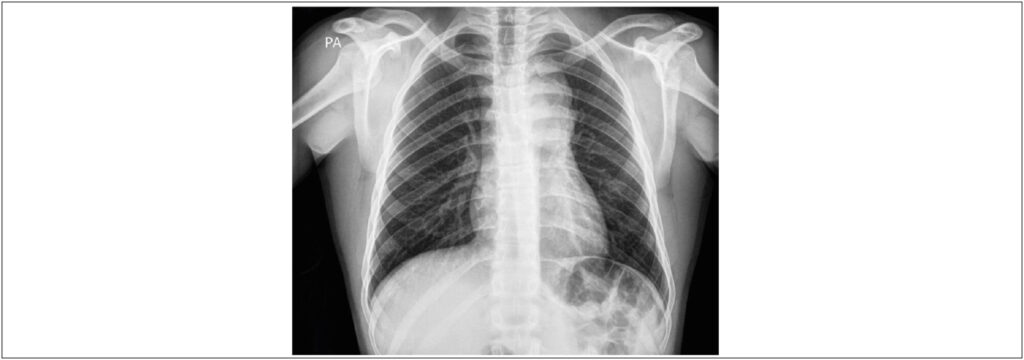

Jovem de 18 anos, sexo masculino, referindo surgimento de adenomegalia cervical esquerda com aumento progressivo há cerca de 1 ano. A tumoração era visível, não móvel, com consistência fibroelástica, indolor à palpação e sem sinais flogísticos. Obteve diagnóstico de linfoma de Hodgkin clássico por meio da biópsia da lesão com estudos anatomopatológico e de imuno-histoquímica (painel positivo para os anticorpos CD15, CD30 e PAX-5). O ecocardiograma transtorácico evidenciou massa de grandes dimensões, com textura heterogênea, envolvendo a artéria pulmonar, o arco aórtico (e seus ramos principais) e a aorta descendente proximal. Não houve evidência, ao Doppler colorido, pulsátil e contínuo, de comprometimento dos fluxos em aorta descendente proximal e nem nos segmentos proximais do tronco braquiocefálico, artéria carótida comum esquerda e artéria subclávia esquerda. A tomografia contrastada de tórax corroborou os achados ecocardiográficos, revelando extensa tumoração mediastinal sólida com aspecto de conglomerado linfonodal, ocupando os compartimentos anterior e médio do mediastino e envolvendo as estruturas vasculares. Não havia sinais de compressão ou invasão.